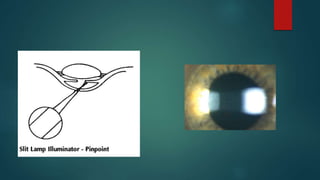

Conical beam(pinpoint)

Produced by narrowing the vertical height of

a parallelepiped to produce a small circular

or square spot of light.

Light source is 45-60 degree temporally and

directed into pupil.

Biomicroscope: directly in front of eye.

Magnification: high(16-25x)